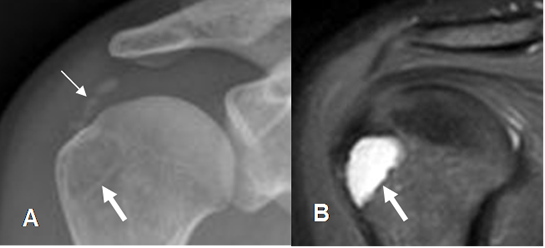

Fig 157. Valoración Pre Qx.

A: Rx AP y B: RM coronal en STIR. Calcificaciones sobre la topografía del tendón supraespinoso, por tendinitis crónica. Sobre la tuberosidad mayor se aprecia imagen radiolúcida y de aspecto benigno, que corresponde a lesión quística confirmada con la RM.